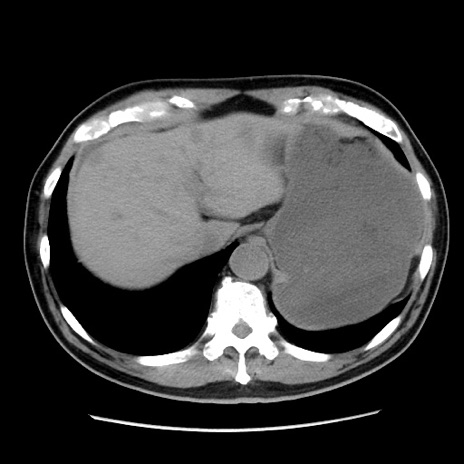

症例16(横断像)

【症例】 70歳代男性

【主訴】 腹痛、嘔吐

【現病歴】 約1ヶ月前より間欠的に腹痛と嘔吐あり、当院消化器内科を受診したところCTで多発する肝臓のLDAを指摘され、精査中であった。以降は消化器症状は安定していたが、2日前より嘔気と腹痛があり、同日より排便・排ガスが消失した。改善認めず、 本日、救急外来を受診した。

【既往歴】 大腸ポリープ切除後。

【身体所見】意識清明・会話良好、BT 36.3℃、BP 127/80mmHg、 P 80bpm、腹部:膨満あり、平坦・軟、上腹部正中および下腹部正中に圧痛あり、反跳痛なし、筋性防御なし。

【データ】WBC 7200、CRP 0.77